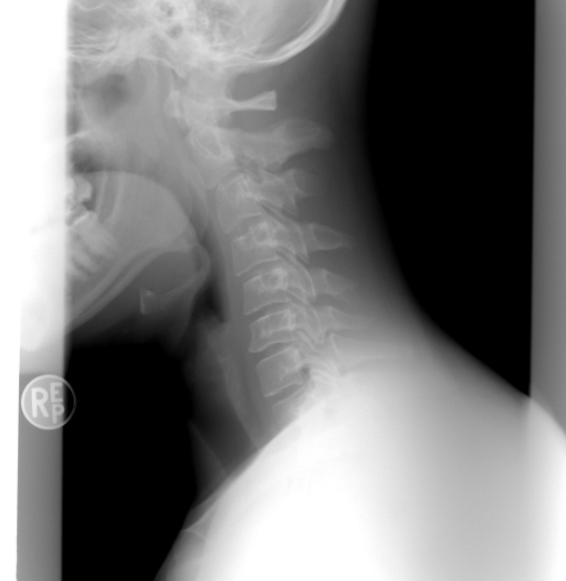

스마트폰를 손에서 놓지 않고, 하루종일 컴퓨터 모니터를 보며 생활하는 현대인들의 고질적인 질병 중 하나가 바로 목디스크입니다. 목디스크는 경추 추간판탈출증이라고도 부르는데, 경추는 7개의 등꼴뼈로 이루어진 척추의 맨 윗부분을 말하며 추간판은 디스크를 말합니다.

하지만 나이가 들어가면서 목의 디스크 또한 노화되기 시작하고 핸드폰, 컴퓨터 모니터를 자주 사용함으로 인해 거북목, 일자목 등 체형의 변화가 오면서, 경추의 디스크가 후방으로 돌출되는 목디스크 질환이 생길 수 있습니다.